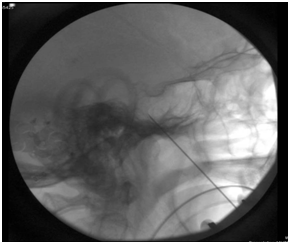

A 38-year-old woman presented with symptoms of TN that began at the age of 34. At first, she presented with optic neuritis and intermittent jaw soreness. Within a period of 4 months her visual symptoms had resolved and her facial pain had progressed along the V1, V2 and V3 distributions of the trigeminal nerve on the right side of the face including (eyes, jaw, teeth and tongue). The patient underwent three dental procedures with no pain relief. Her facial pain was controlled for one year with carbamazepine 600mg daily and pregabalin 300mg daily, however the side effects limited the continued maintenance with this medicine. Gabapentin was also tried, but with poor response. Surgical options were considered. Percutaneous trigeminal ganglion balloon compression (PBC) was performed under neuronavigation as a salvation therapy for acute uncontrollable pain episodes. The patient was admitted to the hospital with acute, constant, and intense pain (Figure 1). Immediately after the procedure the patient experienced pain control. Pregabalin was stopped. After one year, the patient began to experience pain along the V2 distribution. Pain was not well controlled with carbamazepine 600mg a day. Another PBC was done to treat her right V2 pain. Patient pain was controlled.

Figure 1 Neuronavigation conducted for a balloon compression technique approaches to the foramen ovale for the management of trigeminal neuralgia increases goal visualization and potentially decrease the possibility of complications.